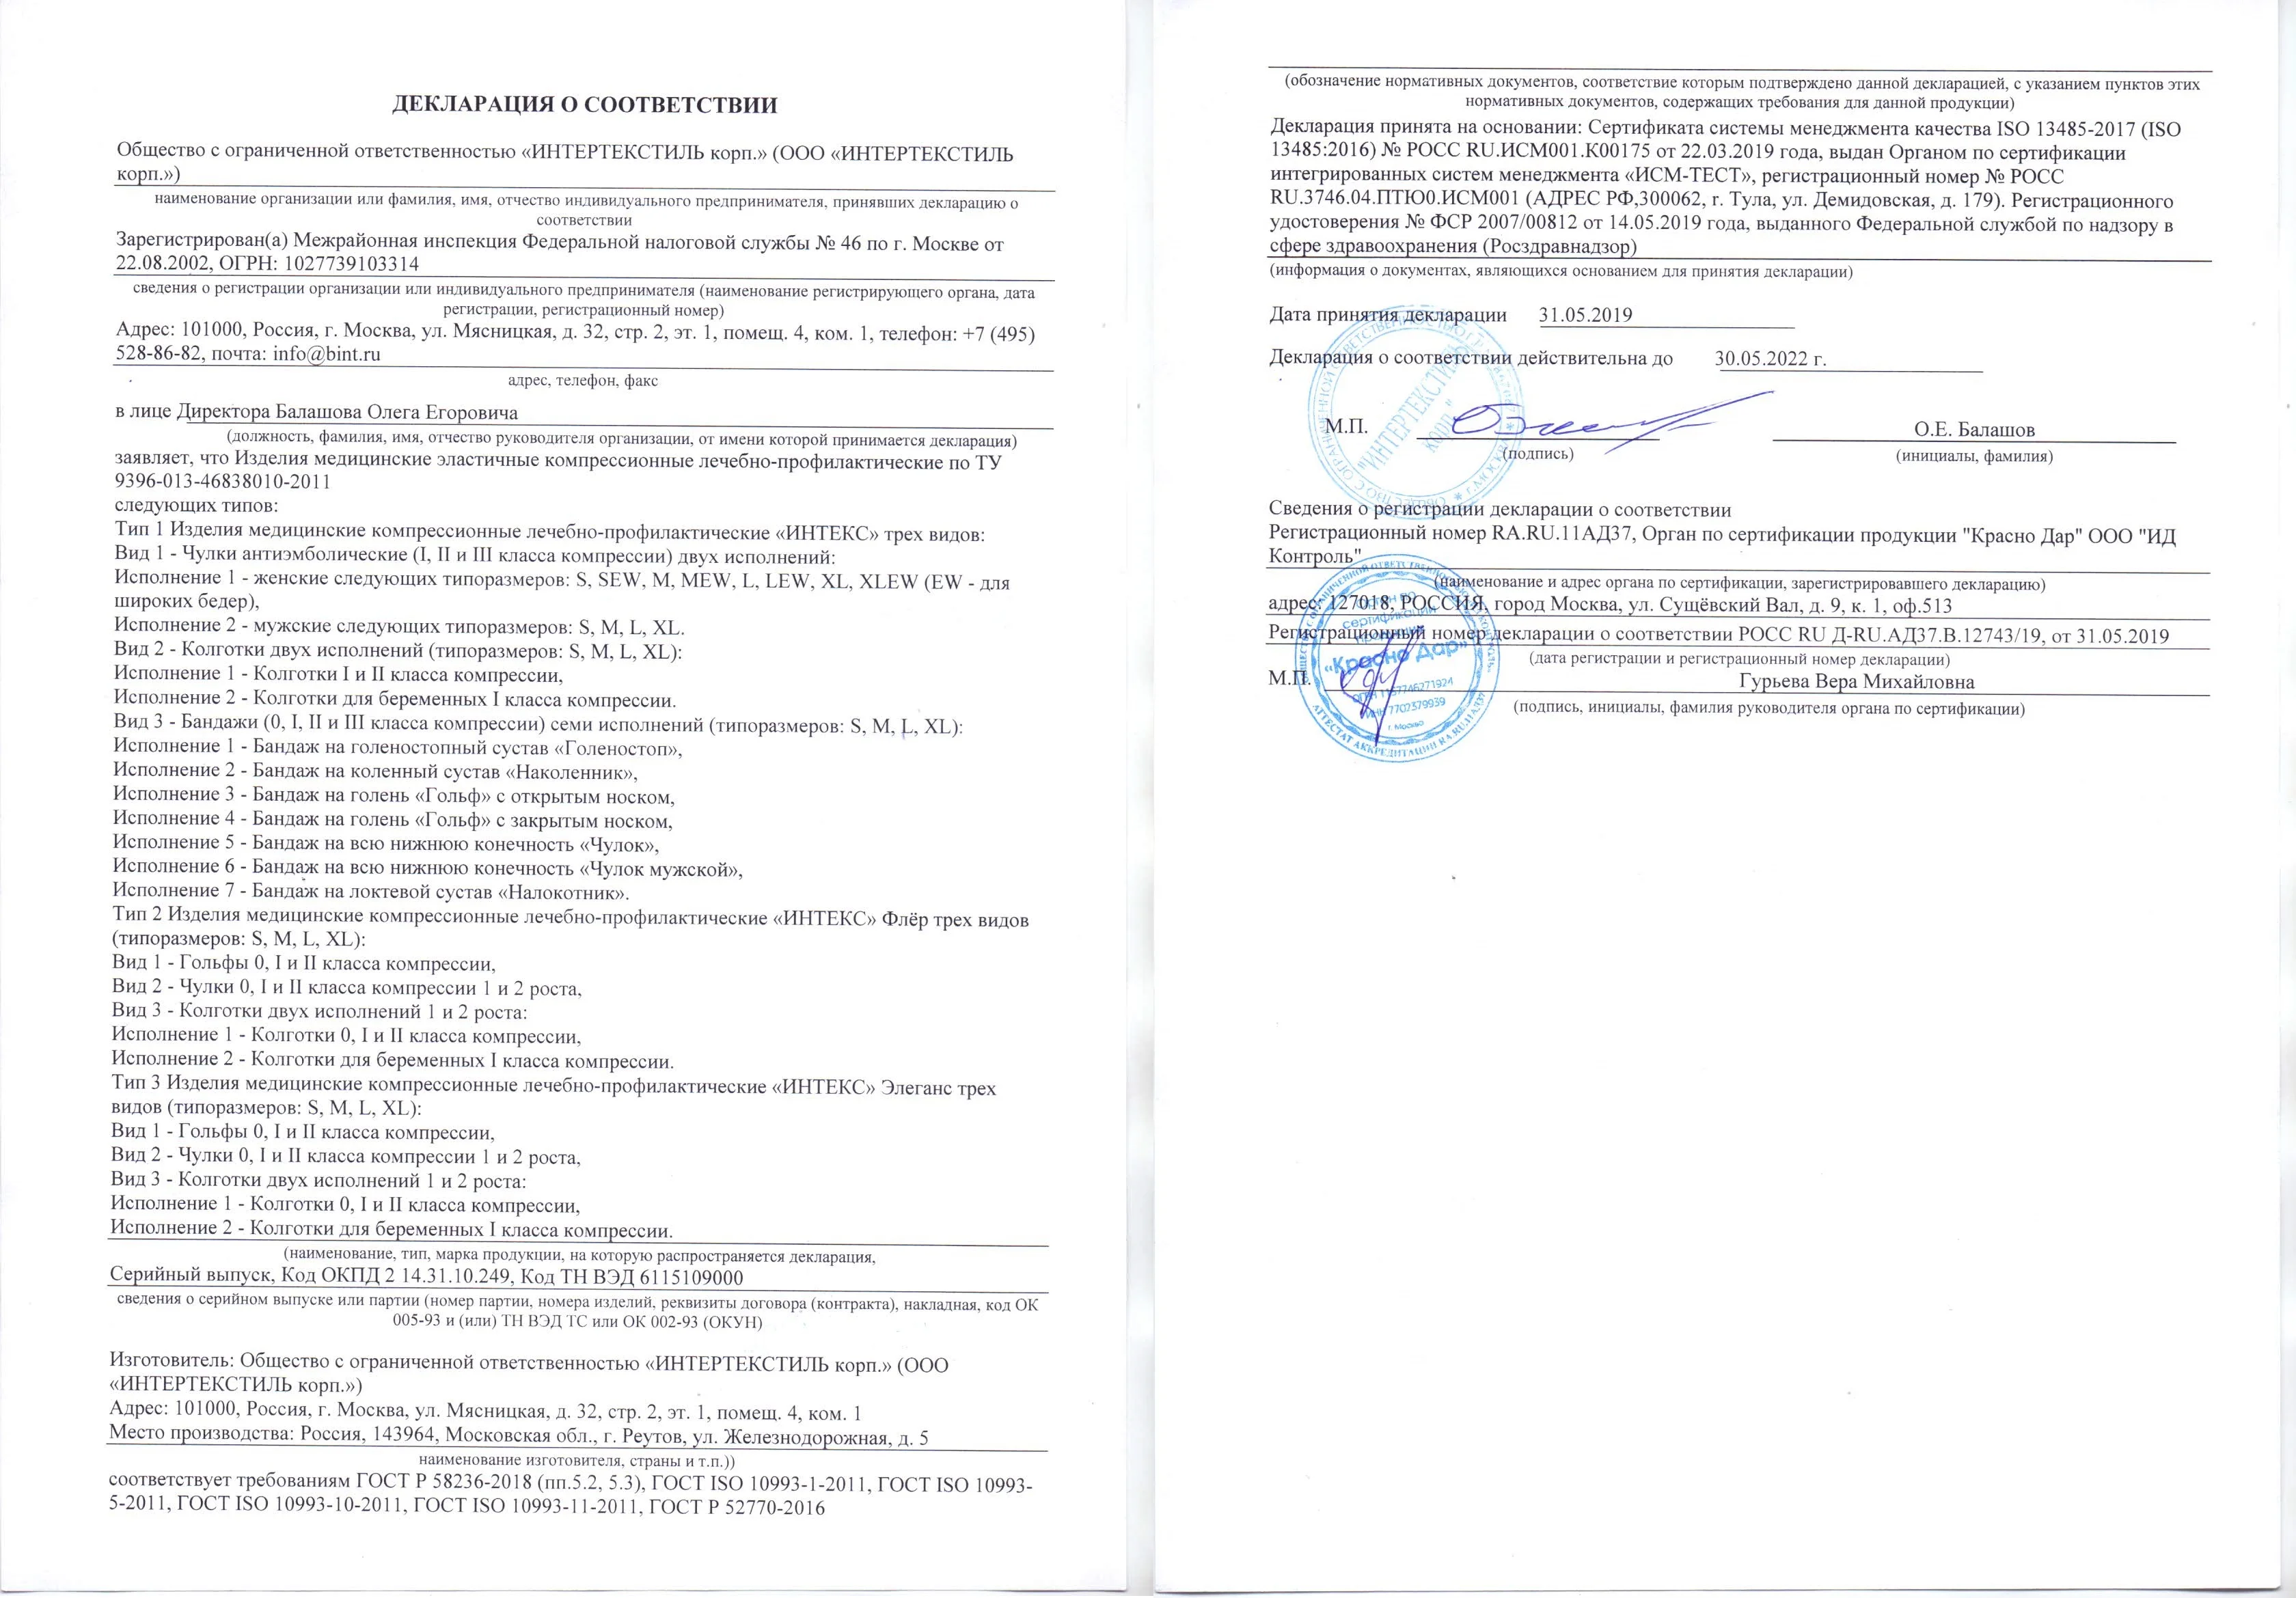

Компрессионные колготки "ИНТЕКС" Элеганс 2 класса компрессии 22-32 мм рт.ст. разработаны, как более доступный по цене вариант премиальных противоварикозных колготок "ИНТЕКС". Снижения цены удалось добиться за счёт использования менее дорогостоящих материалов. При этом качество колготок и их лечебно-профилактические свойства остались на должном уровне.

Основной лечебно-профилактический эффект компрессионных колготок "ИНТЕКС" Элеганс достигается за счёт разницы давления, которое создают колготки на разные участки ног: снизу, на уровне лодыжки давление максимальное, а сверху, на уровне бедра – минимальное. Причём давление плавно уменьшается снизу-вверх, что стимулирует кровоток, препятствует застою венозной крови и предотвращает развитие варикоза.

Колготки "ИНТЕКС" Элеганс 2 класса компрессии применяются по назначению врача в качестве обязательного элемента комплексного лечения хронической венозной недостаточности и варикоза, реабилитации после операций.